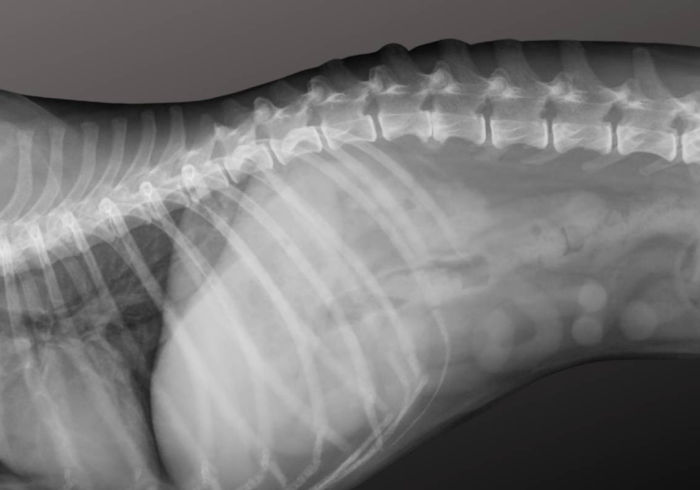

Whereas there’s no strategy to fully stop disk herniations on account of the genetic illness that causes spinal disks to age prematurely and rupture (Intervertebral Disk Disease – IVDD), breeders in Europe have been utilizing Radiographs (X-rays) of the backbone to assist decrease the danger in future generations.

Again screening is completed between ages 2–4 and appears for calcified disks. Fewer calcifications typically means a decrease likelihood of great again issues later in life.

This technique, broadly utilized in Denmark and Finland, includes taking particular radiographs of a Dachshund’s backbone when they’re between the ages of two and 4 to rely the variety of calcified disks. The variety of calcifications offers breeders a sign of how severely the canine could also be affected by IVDD and the way possible they’re to expertise a disk herniation later in life.

The outcomes are reported as a again rating, referred to as the Okay Quantity:

- Grade K0 = no calcifications

- Grade K1 = 1–2 calcifications

- Grade K2 = 3–4 calcifications

- Grade K3 = 5 or extra calcifications.

In 2014, veterinarians Tine Marx and Charlotte Mørck Andersen carried out a Masters thesis on again heath and concluded: Canines with 5 or extra calcified discs had 11 occasions higher threat of disc herniation in comparison with canines with fewer than 5 calcifications. (source)